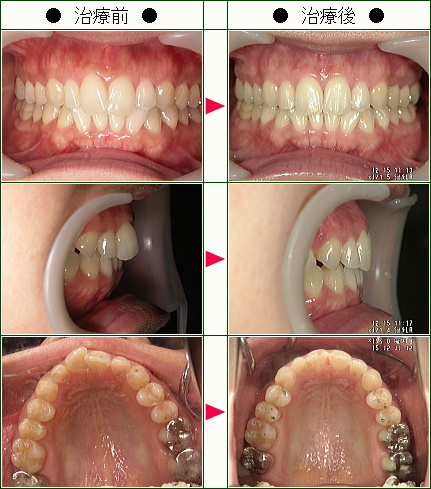

☆歯のデコボコ矯正症例(Y・S様 36歳 女性)